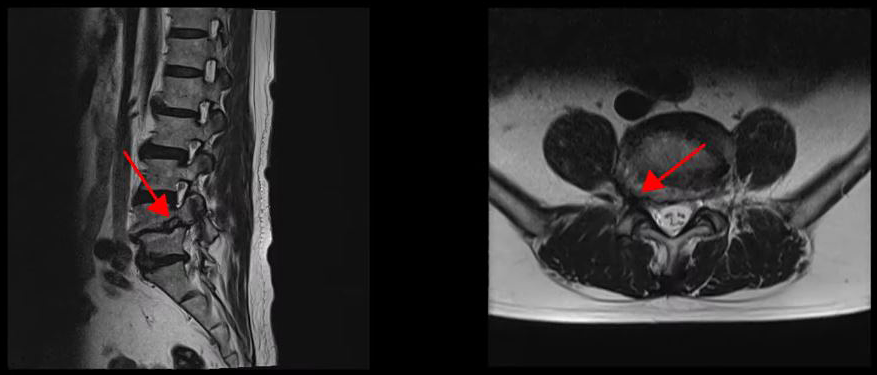

다음은 두 번째 환자분입니다. 이 환자분은 4-5번 오른쪽에 심한 추간공협착증이 있는 상태였고, 2단계의 전방전위증이 있으셨습니다. 이런 심한 협착으로 인해 다리에 마비가 와서 거의 걷지 못하셨습니다. 신경주사도 많이 맞아봤지만 전혀 효과를 보지 못해서 결국 허리협착증 수술을 결심하고 대학병원 등 9군데의 병원에서 진료를 받았지만, 어려운 수술이라고 하면서 병원마다 제시하는 수술방법이 달라 큰 혼란을 겪으셨습니다.